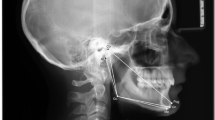

Tracings from lateral cephalograms were conducted by a proficient and calibrated orthodontist as previously described37. The following linear and angular mandibular measurements were evaluated: mandibular total length (Co–Gn), mandibular body length (Go–Pg), mandibular ramus height (Co–Go), Steiner’s SNB angle, and the Y-axis (S.Gn–SN).